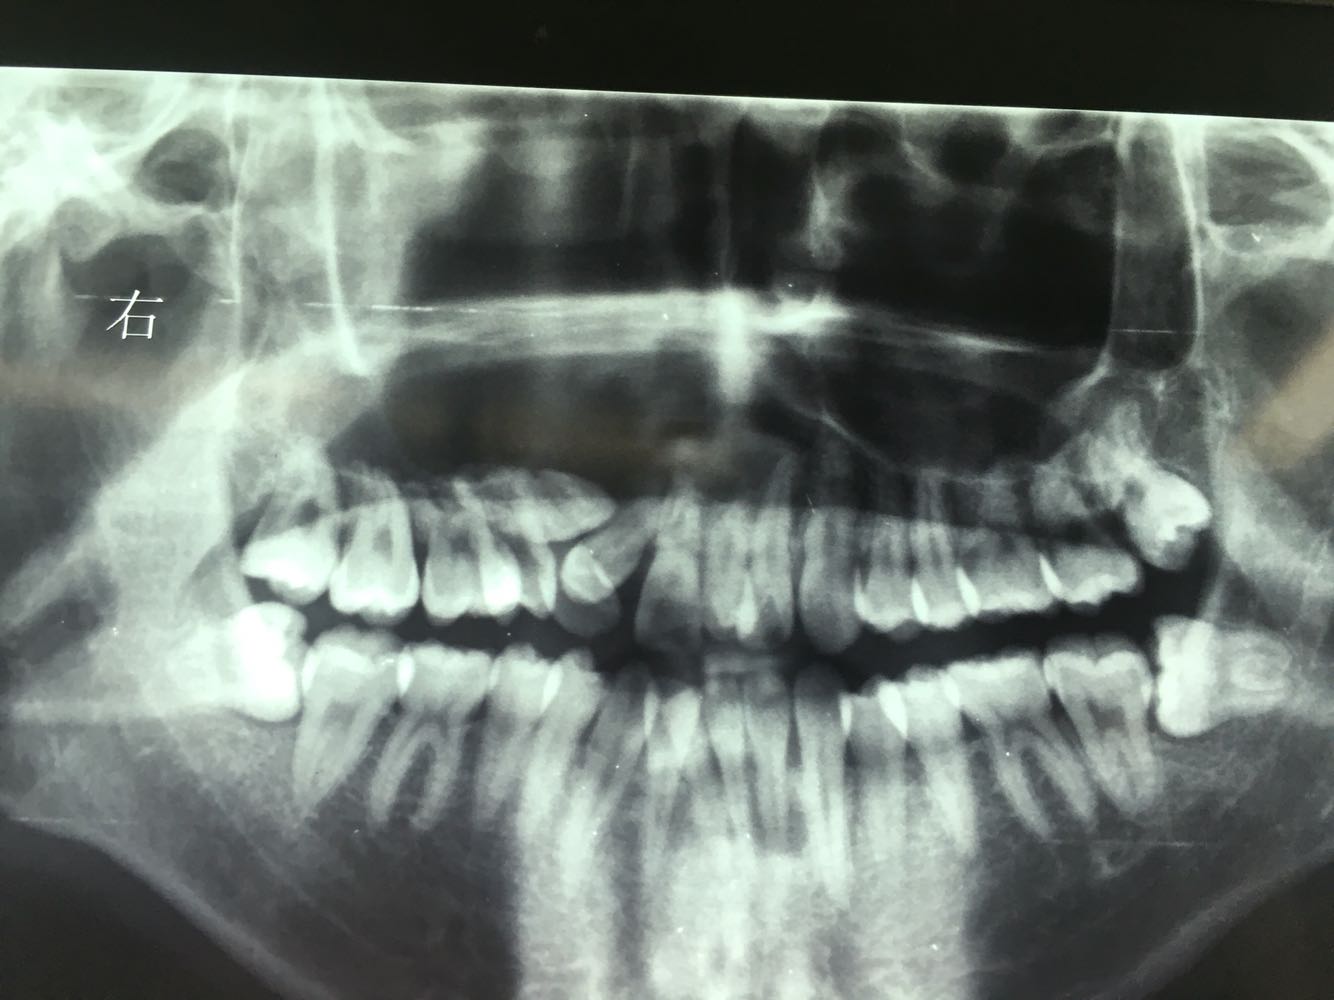

查体:面部明显不对称,右上颌膨隆明显,右鼻翼抬高,眶下区无麻木感,眼球运动自如,13牙齿缺如,16-22牙齿唇侧前庭肿胀,中央扪及波动感,边缘乒乓感,相关牙齿1度松动。 辅查:穿刺,抽得淡黄色液体,全景及CT,上颌骨囊肿,右侧上颌骨骨质大部分破坏

诊断:右上颌骨囊肿,13埋伏阻生。 治疗:开窗减压,拔除13阻生牙齿